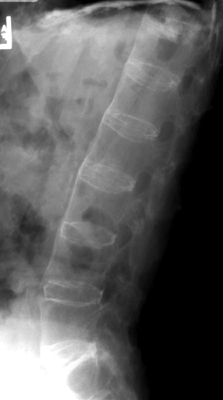

Diagnosis:Ankylosing Spondylitis Discussion:Anterior and lateral radiograph of the lumbar spine which reveals near complete fusion of all of the vertebral bodies. Spinal changes which include squaring of the vertebral bodies and fusion between adjacent levels. The fusion is secondary to syndesmophytes and resembles a bamboo stalk. This is most commonly found in ankylosing spondylitis. References: